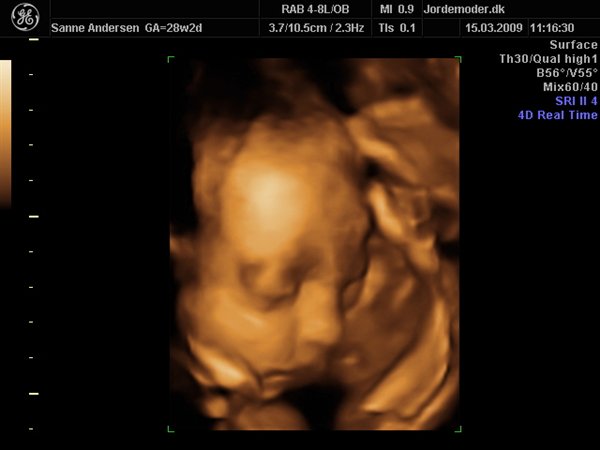

Til venstre ses lillesøster (Celina) i uge 27+3

Til højre på billederne er det storesøster (Bianca) i uge 29+3